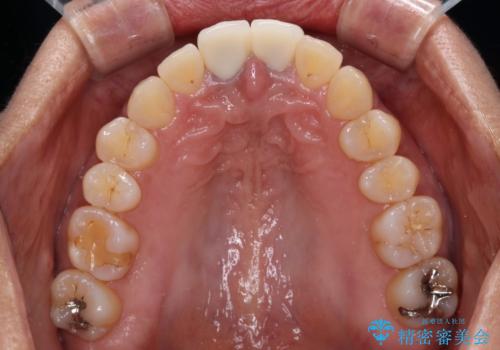

- 前歯のクラウン付近の歯肉が黒く見えることを気にして来院された患者様です。

10年以上前に根管治療を行っており、その際にはラバーダムを使用してしっかりと治療を行っていたとのことで、今回は根管治療は行わずに土台のみを作り替えた上で、オールセラミッククラウンにて補綴治療を行うこととしました。